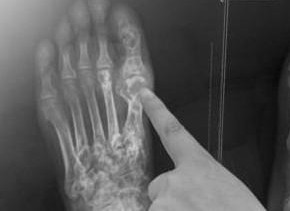

痛風(fēng)治療方法

治療痛風(fēng)的最佳方法包括:調(diào)整飲食,避免高嘌呤食物,保持充足的水分?jǐn)z入;藥物治療,使用非處方藥物緩解疼痛和消炎,或在醫(yī)生指導(dǎo)下使用處方藥降低尿酸水平;生活方式改變,如定期運(yùn)動(dòng)、戒煙和限制酒精攝入等。綜合這些方法能有效控...